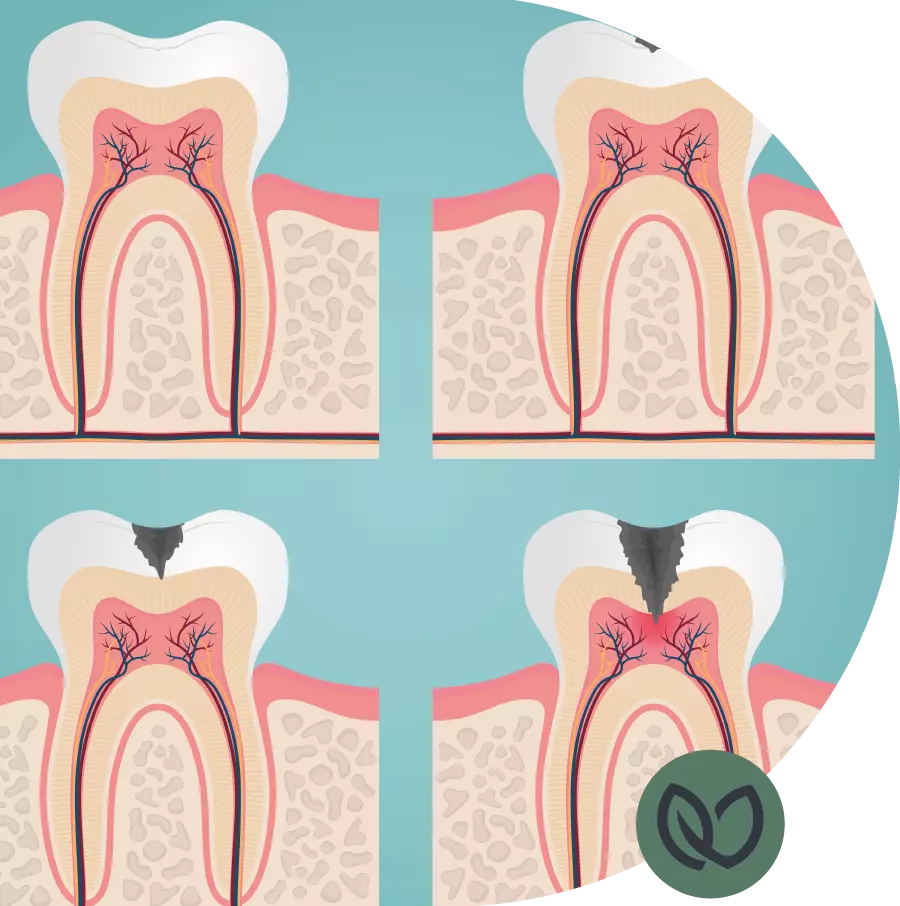

Cariës is een progressieve aandoening waarbij het glazuur van de tanden wordt aangetast door zuren geproduceerd door bacteriën in je mond. Het begint meestal met kleine, onzichtbare plekjes op het glazuuroppervlak, maar kan zich geleidelijk uitbreiden naar dieper gelegen weefsels, zoals het dentine.

Glazuurcariës begint op het buitenste beschermende laagje van je tanden, het glazuur. Deze vorm van cariës hoeft niet altijd behandeld te worden, aangezien het glazuur zichzelf kan herstellen door een goede mondhygiëne en het fluorideren van de tanden. Dentinecariës treedt op wanneer het cariësproces zich verder ontwikkelt en het onderliggende dentine aantast, dat gevoeliger is en kan leiden tot pijn en gevoeligheid. Deze vorm van cariës moet echter wel behandeld worden.